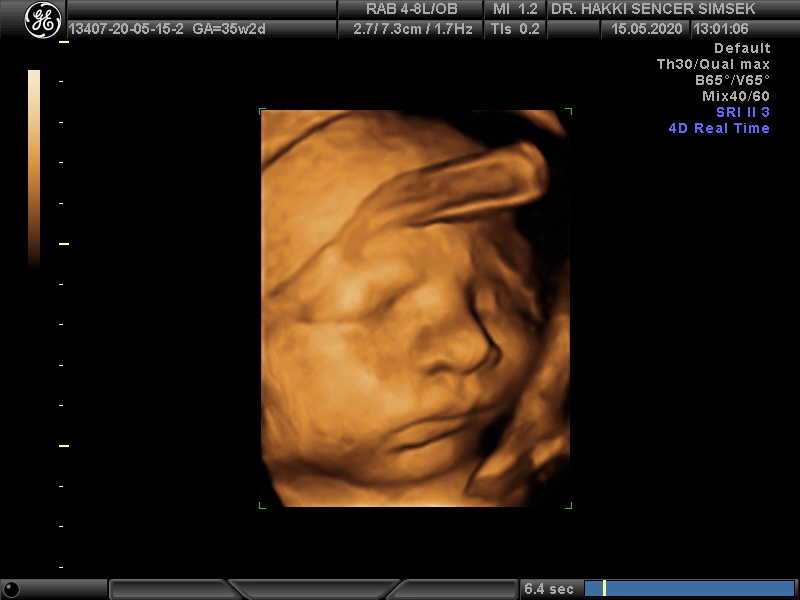

Gebelik Takibi ve Ultrasonun Önemi

Ultrason aleti bizim elimiz ayağımız. Gebelikte de en ufak detayları atlamamak gerekiyor. Bu sebeple teknolojik yenilikl...